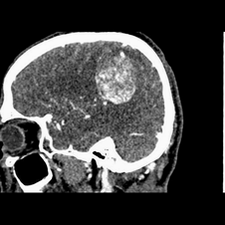

标题: CT25808:男,48岁,头痛多年,近段时间头痛加重伴步态不稳 [打印本页]

标题: CT25808:男,48岁,头痛多年,近段时间头痛加重伴步态不稳

平扫:右颞顶叶病灶呈等低密度伴大面积水肿,脑室受压变形。增强:病灶显著强化。考虑淋巴瘤或黑色素瘤。

血管外皮瘤可能。

1)不排除黑色素瘤可能;建议行mri检查。2)大脑镰下疝。3)脑积水(梗阻性)。